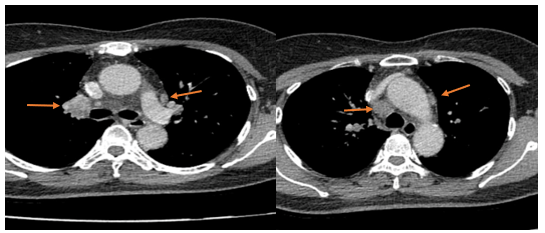

- Cắt lớp vi tính lồng ngực: đám xẹp đông đặc đỉnh phổi phải kích thước 11mm; nhu mô phổi rải rác nốt đặc 5-10mm. Trung thất cân đối có vài hạch 10mm

Hình 6: Hình ảnh cắt lớp vi tính ngực có tiêm: đám xẹp đông đặc đỉnh phổi phải kích thước 11mm (mũi tên xanh nước biển)

Hình 7: Hình ảnh cắt lớp vi tính ngực có tiêm: Trung thất cân đối có vài hạch 10mm (mũi tên vàng). Hạch trung thất giảm kích thước rất nhiều chỉ sau 03 chu kỳ.